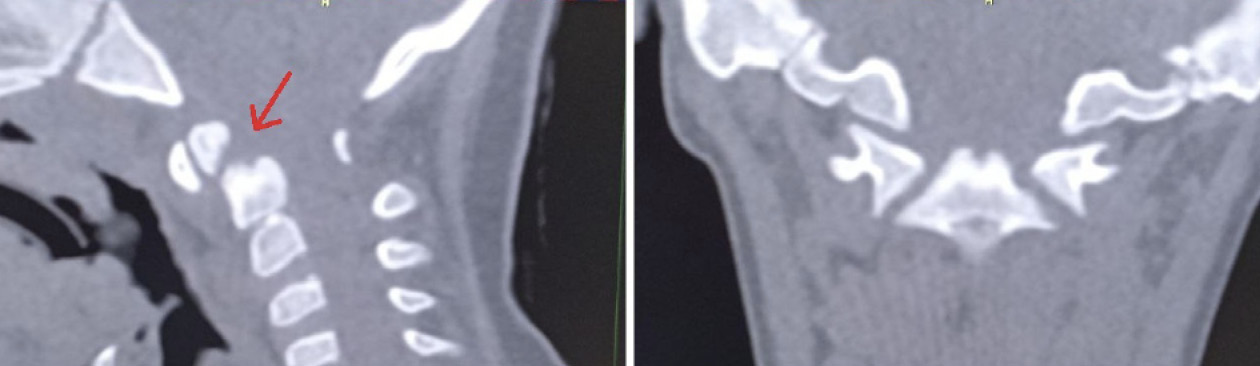

Пациентка Е. 9 лет обратилась на прием с жалобами на ограничение поворотов головой. Со слов матери, в мае 2018 г. ребенку проводилось оперативное лечение по поводу травмы шейного отдела позвоночника. Медицинские заключения не были предоставлены. При осмотре ребенок с синдромом Дауна. Голова по средней линии, пальпация области шейного отдела позвоночника безболезненна, объем пассивных и активных наклонов головы соответствовал нормативным значениям. При этом амплитуда пассивных и активных ротационных движений в шейном отделе позвоночника составила 15° и 20º в каждую сторону соответственно. При последующем ортопедическом осмотре было выявлено нарушение осанки по типу «сутулая спина» по Штаффелю. По данным анализа представленного диска с результатами ранее проведенной мультиспиральной компьютерной томографии шейного отдела позвоночника (дата исследования – май 2018 г.) был выявлен перелом зубовидного отростка С2 позвонка типа 1 по классификации L. D. Anderson и R.T. D'Alonzo, со смещением верхушки зубовидного отростка кпереди [9]. Плоскость перелома зубовидного отростка аксиса косая, края отломков неровные, нечеткие, диастаз между отломками неравномерный (рис. 5).

Рис. 5. Компьютерная томография шейного отдела позвоночника, сагиттальный срез (А), фронтальный срез на уровне зубовидного отростка С2 позвонка (Б). Стрелкой обозначено место перелома зубовидного отростка С2 позвонка